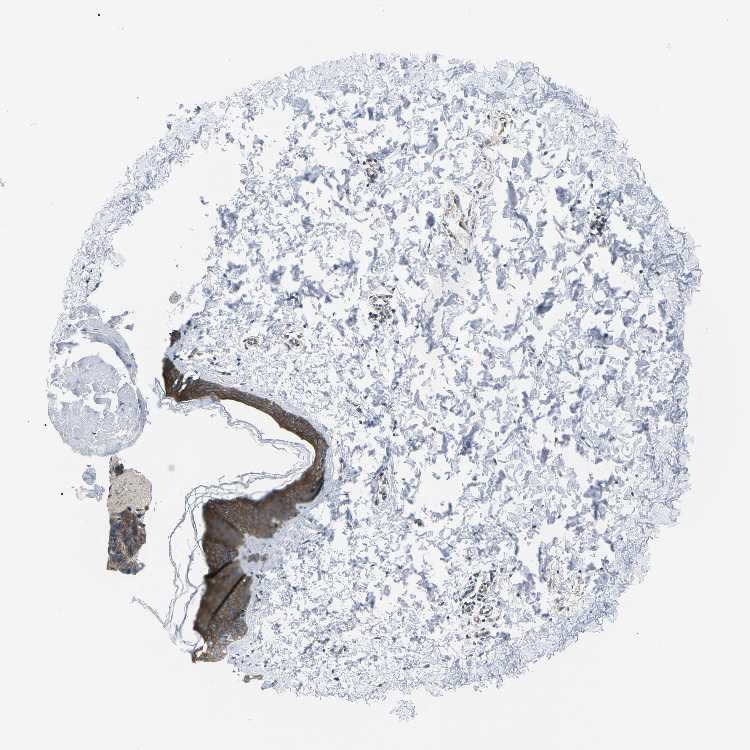

SKIN 1 - Antibody stainingi

Antibody staining in the annotated cell types in the current human tissue is reported as not detected, low, medium, or high, based on conventional immunohistochemistry profiling in selected tissues. This score is based on the combination of the staining intensity and fraction of stained cells.

Each image is clickable and will lead to virtual microscopy that enables deeper exploration of all samples and also displays staining intensity scores, fraction scores and subcellular localization as well as patient and tissue information for each sample.

Antibody CAB016307

Langerhans Medium

Fibroblasts Medium

Keratinocytes Medium

Melanocytes Medium

SKIN 2 - Antibody stainingi

Epidermal cells High